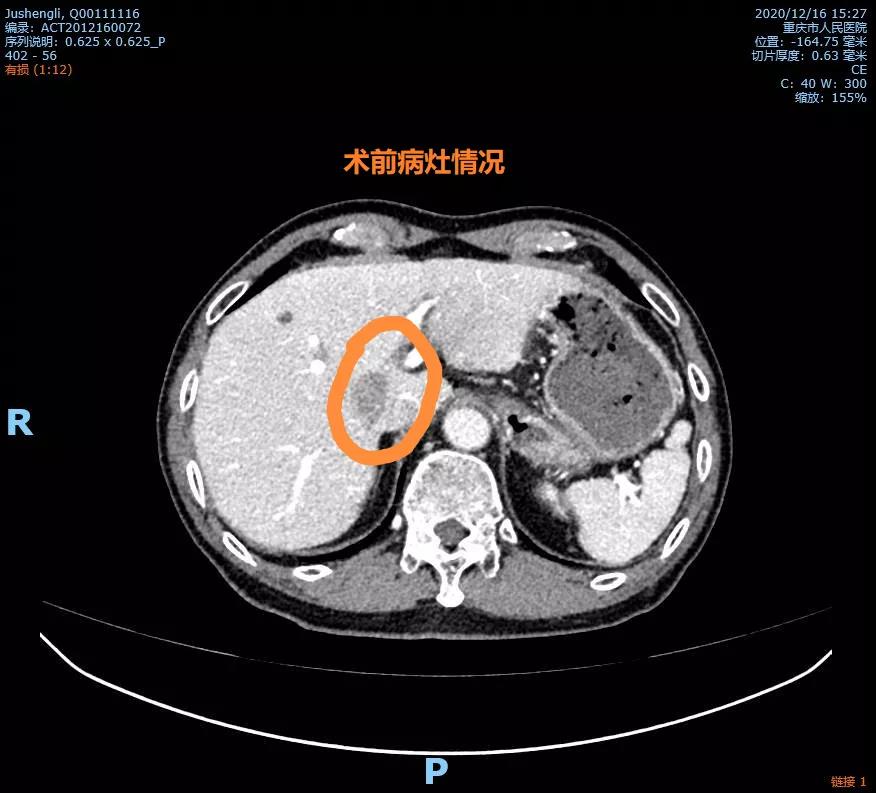

术前病灶位置术前病灶位置

“肿瘤紧邻周围重要血管组织,可能已经造成侵犯。但我觉得肿瘤和血管之间还有可以操作的空间。如果采用我们自己独创的分离方法,精细化操作就有可能将血管全部分离开来,对肿瘤进行完整切除”,王槐志主任一边讲述自己的判断依据,一边演示治疗方案。“请迅速安排三维重建检查,待结果出来进一步确定手术方案”。很快,初步方案得到了谢炜、郑明友等教授的支持。